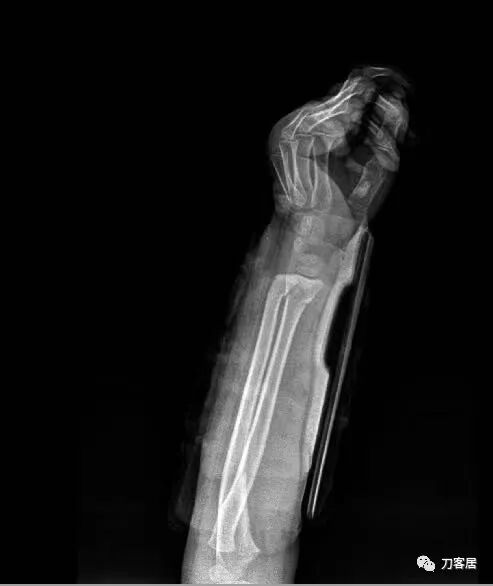

下面是这个6岁孩子,尺桡骨远端双骨折的术前及术后片子和外观照片。

2.  这个骨折处理起来也很简单,单纯的打石膏托或者中医的小夹板,或者正规的包括腕关节和肘关节的管型石膏外固定4周即可治愈该骨折。实在不行,如果这个孩子比较听话,不太调皮的话,用一本书,一个三角巾悬吊固定4周,都可以治愈该骨折。但是给这个患者用外固定架做了手术,而且桡骨远端的几颗克氏针距离骨折线太近,其中一枚克氏针进入到骨折间隙内。从这个术中图片来看,术者的外固定手术技术也有待于进一步的提高。毕竟术者应该还很年轻。从X线片来看,前臂及手的尺侧有不透光影,应该还使用了外固定石膏绷带托,而且我猜测应该是高分子的石膏绷带托,这个是纯属猜测,不一定是对的,不过如何解释前臂尺侧的不透光影呢?如果真是用了石膏绷带外固定的话,那为啥要做手术呢?外固定架术后就不该再用石膏绷带托辅助了。